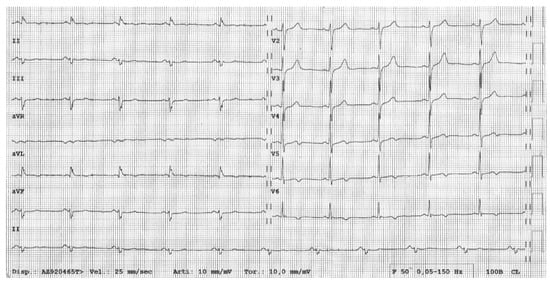

- ECG repolarization anomalies like T-wave inversion (TWI) in right precordial leads (V1-V4);

- ECG depolarization anomalies like the epsilon wave or delayed terminal activation duration (TAD) of QRS;

- VAs, such as frequent premature ventricular beats or VTs, having a left bundle branch block and superior axis morphology;

- RV morpho-functional abnormalities (segmental RV wall motion abnormalities plus RV dilatation or dysfunction) on imaging tests such as contrast echocardiography, CMR or cine-ventriculography [5]. The ECG features typically precede the morpho-functional abnormalities, becoming more extensive with the progression of the disease. Interestingly, a higher RV dilatation and lower RV ejection fraction are associated with the extent of TWI toward left precordial and inferior leads, and prolonged TAD [60].